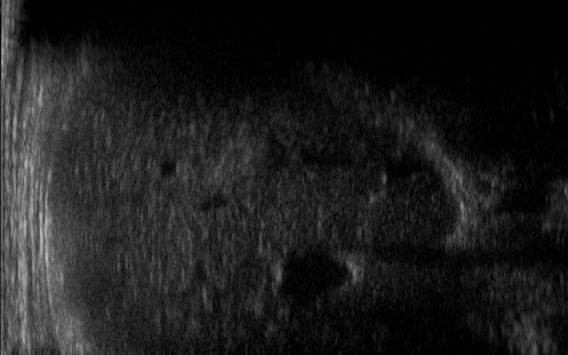

We also verify the robustness of our method on images at different brightness. Characterising the brightness of an image as the average value of all pixels, we test images with high and low brightness on different anatomical districts and up-sampling factors. Figs. 10, 11 show that the prediction performed with our trained network is robust to different values of image brightness, never lowering the output accuracy or generating artefacts. Comparing the input and the prediction of our network with the target image, we improve the PSNR value from 43.46 to 43.55 with high brightness images from the abdominal district 2X up-sampling, and from 31.01 to 31.48 with low brightness images from the obstetric district 4X up-sampling.

For the experimental part, we consider the Esaote data set, which contains more than 10K US images at different resolutions, and is acquired from different anatomical districts (e.g., obstetric, cardiac). Given a high-resolution image (i.e., the target) acquired by the probe, we build the corresponding low-resolution image by removing one line each 2 (0.5X) or 4 (0.25X). This approach is consistent with the acquisition of the US image, where the probe can acquire at the full, half, or a quarter of the maximum number of beamlines, depending on the activation of the piezoelectric crystals. We up-sample the low-resolution images through Cubic Convolution at 2X (applied to 0.5X low-resolution) or 4X (applied to 0.25X low-resolution). Then, we use the couples of up-sampled and target high-resolution images to analyse the proposed framework, through the training and the prediction of the learning-based network, with a specialisation in anatomic districts.

We train each learning-based network (custom-WDSR) with 1.5K images, where the input is the outcome of the selected up-sampling method (i.e., Cubic convolution), and the target is the original high-resolution image. Indeed, input and target images have the same resolution, as the reconstruction of the missing lines has been already performed by Cubic convolution. Figs. 3, 4, and 5 show the results of the network prediction, compared with the input and the target images. Target images correspond to spatial high-resolution images; input images are the outcome of the up-sampling interpolation, which is applied to spatial low-resolution images (i.e., the down-sampling along the lateral direction of high-resolution images); prediction images represent the output of the neural network.

Our framework visually improves the results, in terms of blurring and artefacts. This result is more evident in the magnification of the ear of the foetus (Fig. 3), the mitral valve (Fig. 4), and the mass edges (Fig. 5). Fig. 6 shows the error image of the three anatomical districts with both 2X and 4X up-sampling factors, with the maximum error in the scale . The error is more evident in the contours of the anatomical structures; moreover, the abdominal district shows a smaller error than the cardiac and obstetric ones. We underline that the view for each image is scaled to its maximum, to improve the visualisation of the error.